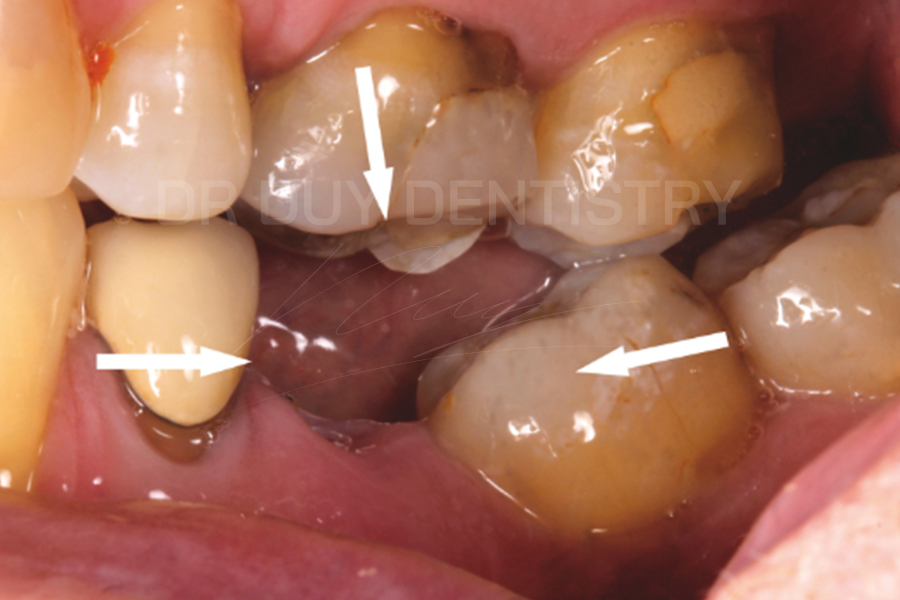

- Sai lệch khớp cắn do các răng lân cận nghiêng, lệch cũng như răng số 6 hàm đối diện trồi vào khoảng trống do mất răng.

- Các răng di lệch gây bất hài hòa thẩm mỹ nụ cười.

Mất răng số 6 không chỉ ảnh hưởng đến chức năng ăn nhai mà còn ảnh hưởng đến các răng lân cận, xương hàm, khớp và toàn bộ hệ thống nhai. Do đó, khi mất răng, trẻ cũng như người lớn nên được điều trị càng sớm càng tốt để ngăn ngừa các biến chứng về sau.